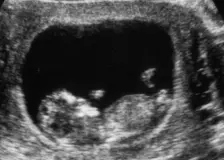

Z pusy dítěte šla obrovská bublina. Lékaři kvůli ultrazvuku těhotné ženy spustili rudý poplach

Maminka se zděsila, když během ultrazvukového vyšetření zjistila, že její dítě má na pusince nádor, který vypadá jako bublina. Rozhodla se však zariskovat. Očekávání potomka je jednou z nejradostnějších chvil v životě člověka. Žádný nastávající rodič si …